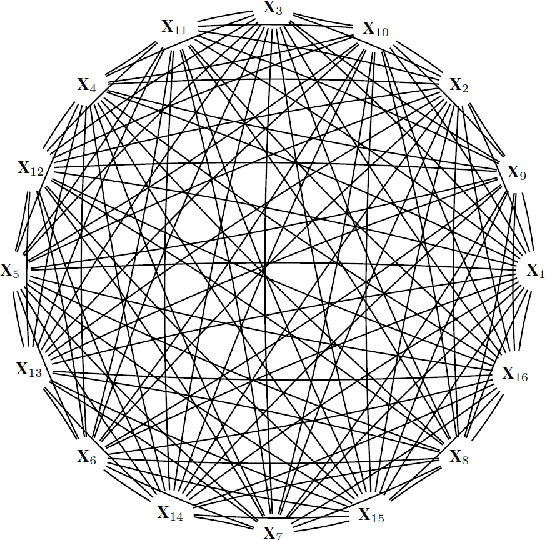

Abstract:Recently, the intervention calculus when the DAG is absent (IDA) method was developed to estimate lower bounds of causal effects from observational high-dimensional data. Originally it was introduced to assess the effect of baseline biomarkers which do not vary over time. However, in many clinical settings, measurements of biomarkers are repeated at fixed time points during treatment exposure and, therefore, this method need to be extended. The purpose of this paper is then to extend the first step of the IDA, the Peter Clarks (PC)-algorithm, to a time-dependent exposure in the context of a binary outcome. We generalised the PC-algorithm for taking into account the chronological order of repeated measurements of the exposure and propose to apply the IDA with our new version, the chronologically ordered PC-algorithm (COPC-algorithm). A simulation study has been performed before applying the method for estimating causal effects of time-dependent immunological biomarkers on toxicity, death and progression in patients with metastatic melanoma. The simulation study showed that the completed partially directed acyclic graphs (CPDAGs) obtained using COPC-algorithm were structurally closer to the true CPDAG than CPDAGs obtained using PC-algorithm. Also, causal effects were more accurate when they were estimated based on CPDAGs obtained using COPC-algorithm. Moreover, CPDAGs obtained by COPC-algorithm allowed removing non-chronologic arrows with a variable measured at a time t pointing to a variable measured at a time t' where t'< t. Bidirected edges were less present in CPDAGs obtained with the COPC-algorithm, supporting the fact that there was less variability in causal effects estimated from these CPDAGs. The COPC-algorithm provided CPDAGs that keep the chronological structure present in the data, thus allowed to estimate lower bounds of the causal effect of time-dependent biomarkers.